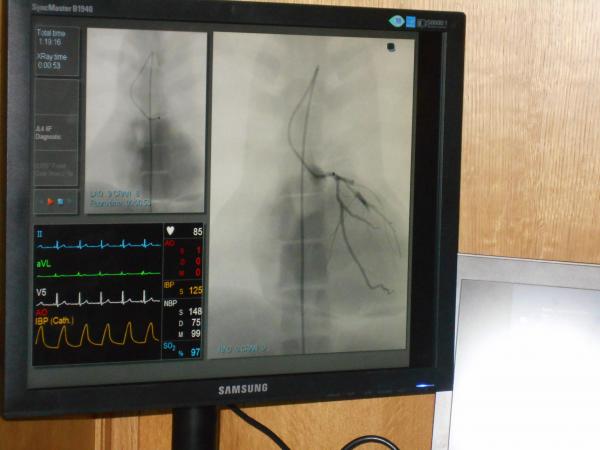

„Гострий інфаркт міокарду – це закриття артерії серця, тому важливо її відкрити. Чим швидше це відбудеться, тим кращим буде результат. Фармацевтичні способи відкриття не можуть бути найбільш ефективними, адже не кожен тромб розчиняється. Тому на сьогоднішній день основний світовий стандарт лікування – механічне відкриття, тобто катетеризація артерій серця і встановлення всередині коронарної артерії металевого каркасу, так званого стенту”, – розповідає провідний науковий працівник Інституту кардіології ім. Стражевського, головний позаштатний спеціаліст МОЗ України зі спеціальності „Кардіологія” Максим Соколов.

„Інфаркт – не лише медична, але й соціальна проблема, це проблема інформування населення, проблема кожного з нас. У міській лікарні надають допомогу пацієнтам з цілої області. Тут проводять стентування пацієнтам з гострим інфарктом міокарда та елевацією сегмента СТ. Такими виїзними засіданнями ми хочемо показати, що впроваджуючи правильну терапію, впроваджуючи новітні технології, ми зможемо зменшити летальність від гострого інфаркту міокарда з 14%, як зараз є в Україні, до 5%, як в інших країнах Європи. В країні за минулий рік зареєстровано майже 41 000 випадків інфаркту міокарду, половина з них потребували застосування стентування”.